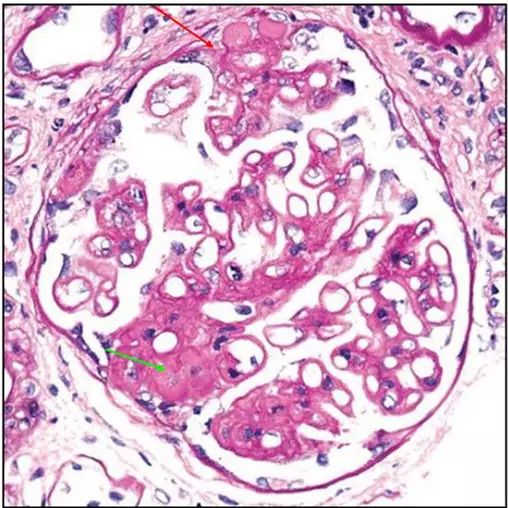

肾内病理图解 | 膜性肾病

肾内病理图解 | 膜性肾病